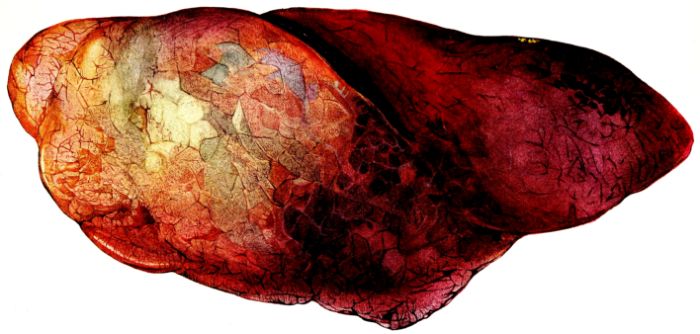

FIG. XIII. AUTOPSY NO. 96. RIGHT LUNG. A WATER COLOR DRAWING OF A GROSS LUNG IN THE ACUTE STAGE. NOTE THE SIZE OF THE LUNG, THE HEMORRHAGES ON THE PLEURAL SURFACE, AND THE BLUE AREAS OF CONSOLIDATION.

FIG. XIV. AUTOPSY NO. 96. LEFT LUNG. NOTE ITS SIZE AND THE PATCHY CONSOLIDATION.

19The lungs are extremely voluminous (12, 17) due in part to an accumulation of liquid within them. This finds its way into the trachea and completely fills the latter structure with blood-stained, syrupy fluid, with purulent material, or with a mixture of these (2, 90, 107, 157, 162). At first the pleural surface is smooth and often quite even, but on closer inspection, a minute granulation is suggested. In many cases even close examination does not allow the conclusion that an exudation of anything but serum has occurred through this membrane, except in localized foci. These foci more frequently involve the interlobar pleura and that of the lower lobes (112, 143). The volume of the lungs, often great enough to obliterate the pericardial area, is one of the two most characteristic features of the external examination. The other feature is their color. Small, bright red hemorrhages may occur anywhere. The larger patches are the most striking. Violet, purple, or dark brown areas, irregular in shape and distribution, are more frequently found on that portion of the pleura over the lower two-thirds of the lung. Between the deeply colored zones, there are pale pink areas which involve the lowermost edge to the least degree, the anterior margin somewhat more, and the apex of the lung most of all. The darker portions just referred to may project above the surface and may be circumscribed, resembling huge, fresh hemorrhagic infarcts (41, 108). The alveolar walls are not seen through the pleural surfaces in these darker zones. The pale pink areas, usually at the level of the more intensely colored zones, may be elevated and the dilated air sacs are distinctly made out through the pleura (Fig. XIII). At the hilum, the lymph glands are large and soft. When cut, fluid escapes and is often blood-stained. The cross section may present a distinct, diffuse, hemorrhagic appearance (162). At the hilus, too, the lymphatics, distended here and there over the surface of the pleura, are most affected. The congested bronchial mucous membrane and the exudate in these structures has been described.

After removal, the lung retains its shape, but is more flaccid than the consolidated lung of lobar pneumonia. It cuts with very little resistance and immediately a large amount of a syrupy, pink fluid escapes and obscures the entire area. With the fluid scraped away, the variations in the consistency of the lung become visible. The pale areas around the borders and chiefly at the apex in which the air sacs are discernible with the naked eye, sink slightly below the remainder of the surface, and the pleural edge inverts. The individual lobules of the lung in these areas are more conspicuous than normal, because the interstitial tissue bearing the lymphatics and vessels, as well as that around the bronchi and larger blood vessels, does not lose its edematous appearance as quickly as the alveoli (40, 92, 110, 164), and, consequently, these grey lines and points stand up somewhat more prominently.[6] In contrast with the paler areas which are prone to slight collapse, the remainder of the cross section retains its more smooth and even surface. The alveolar walls are not distinctly made out, but the terminal bronchioles often make themselves evident by the nature of the material which is within and by their distinct dilatation (1, 67, 110, 149, 162). The more firm areas stand out, too, on account of their difference in color. The scheme is not unlike that seen on the pleural surface, and while dark, almost black, infarct-like areas occur on the cut surface, the solid areas are more likely to be translucent, dull, light red, brown or even grey. They have a surface similar to a very fresh, tuberculous, gelatinous pneumonia, but the color differs from the cloudy grey of the latter on account of the admixture of blood in the exudate and the great congestion of the vessels (Fig. XIV).

The well developed post-mortem muscular rigidity, the lividity of the dependent parts, of the face with its mucous membranes, and often of the trunk, the jaundice variable in extent, the crusts of blood on the nares and mouth, and the splanchnic dilatation are features which prepare for the gross picture presented by the thoracic organs. The increased moisture within the pleural cavities associated with the even, translucent pleural surface, whose dilated lymphatics become more and more prominent towards the hilum, the large succulent lymph glands, and the exudate in the bronchial tree, are all striking, but more characteristic of the gross picture, is the great increase in volume of the lung itself, mottled 20with brilliant colors. The lung, too, is very wet and on section, after the syrupy, blood-stained fluid escapes from the less definitely consolidated zones, the latter appear, not as the usual granular, firm areas of hepatization, but have more the consistency of a gel, and also its translucence. Characteristic of this disease as these changes may be, the specificity of the fundamental lesion in the respiratory tract, becomes more emphatic after study of its histology (92, 162).